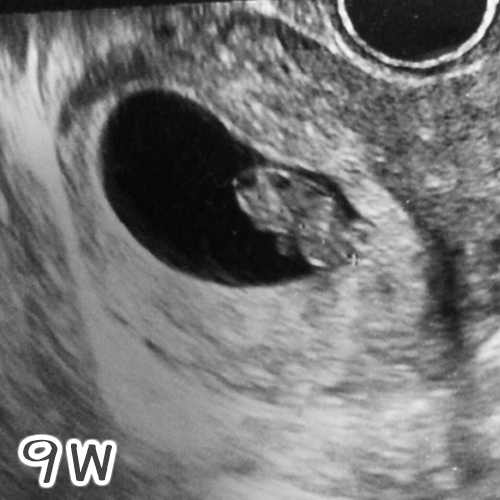

その後は超音波検査。

大きさは1.95cmになり、形もデコボコと変化が見られ

ちょっと人間らしい形になってきたかな( 'Θ' )